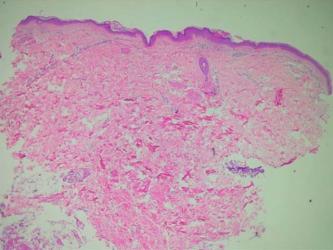

Identificación. Paciente femenina 10 años

Natural y procedente: Soacha-Cund

Ocupación: estudiante.

Motivo de Consulta: “Tiene unas ronchas”

Enfermedad Actual: Inicio espontáneo hace 3 meses de lesiones pruriginosas, descamativas